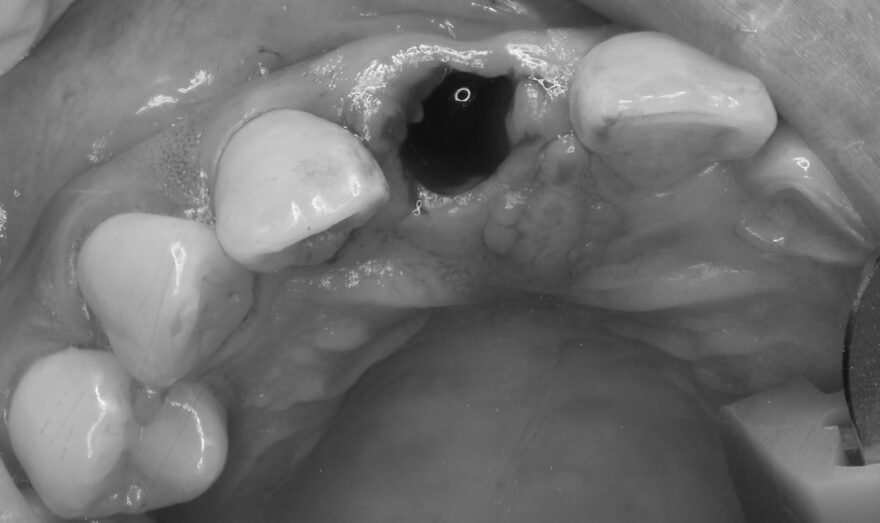

オペ中の口腔内写真とCT写真